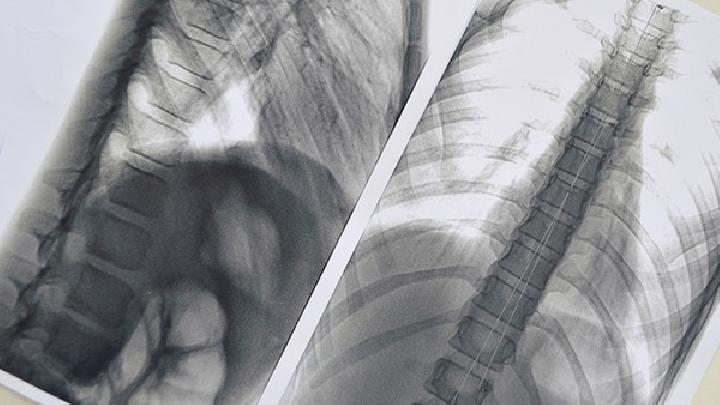

小细胞肺癌检查费要多少钱?患有小细胞肺癌后不要过度担心,及时到正规医院就诊,及时检查治疗是可以痊愈的,那么很多人就会问了,去医院检查要多少钱呢,那么今天我们就一起来了解一下:

收费是跟城市而言的,医院的级别不同收费也不同,一般检查费用大概一千至三千元左右,遵医嘱正常进行检测就可以确定。

检查费用不能一概而论的,要根据病人的具体病情才能决定的,每个病人的症状不一样,检查的项目也不相同,小细胞肺癌疾病受很多因素的影响与制约,与小细胞肺癌发现时的严重程度、治疗方案、并发症的有无、治疗地区和医院的不同而有所差异,因此治检查费用是不能用一个具体数字来概括的,应分病情,分情况而定。